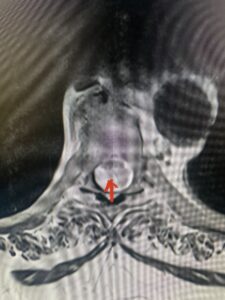

This 47-year-old male who four months prior was lifting weights developed sharp pain in his neck. After that he developed progressive numbness in his arms, neck pain and headache. He said that the right arm was worse than the left. On examination the patient had long tract weakness on the right side which included his triceps, finger extensors, hip flexors, and dorsiflexors. The patient did not have hyperreflexia. MRI (Fig. 2) demonstrated a massive, extruded disc herniation with severe cord compression. The patient because of progressive myelopathy and spinal cord compression was indicated for anterior cervical discectomy and fusion at C4-5 (Fig. 3). Patient had significant improvement of weakness and numbness post operatively.

Fig: 2b Axial T2-weighted cervical MRI demonstrating spinal cord compression from C4-5 herniated disc (red arrow)